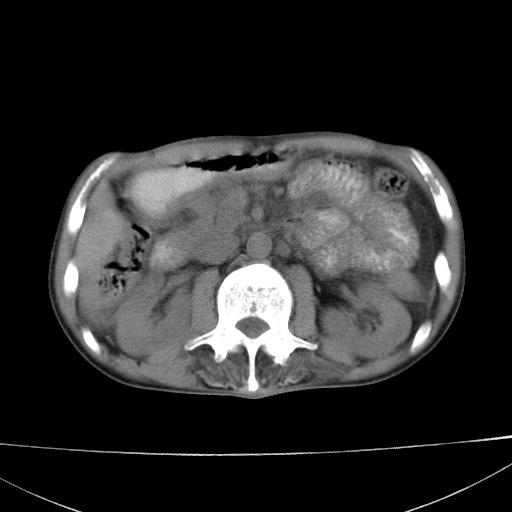

患者 男  41岁,右上腹痛伴腹泻10天,8年前有乙肝,本次b超查肝右叶占位来做ct ,请会诊!

肝硬化\\脾大\\门静脉高压,胃底静脉曲张可能性大.肝右叶肝癌肝内转移,建议增强.左侧小结石.

肝右叶肝癌肝内转移,建议增强

支持肝癌伴肝内转移,脾大,门静脉高压,胃底静脉曲张。

1)考虑肝癌;建议行ct增强扫描检查。2)脾大,门静脉高压,胃底静脉曲张。3)左肾小结石。

1)考虑肝癌及门脉瘤栓,建议行ct增强扫描检查。2)脾大,门静脉高压,胃底静脉曲张。3)左肾小结石。

结合病史;考虑肝癌。门静脉高压,脾大。胃底静脉曲张。

1)考虑肝癌;2)脾大,门静脉高压,胃底静脉曲张。3)左肾小结石。建议行ct增强扫描检查。